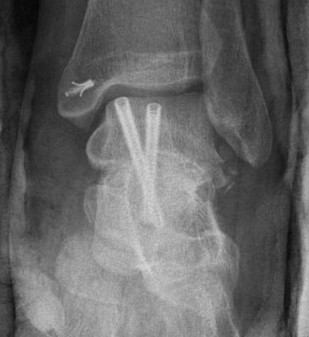

Cannulated screws

Xrays

| AP | Lateral | Canale View |

|---|---|---|

| Entry point of the screws |

Evaluate neck reduction

|

Evaluates the neck reduction |

Lateral off articular surface Medial through articular cartilage |

Depth of screws |

Beam angled 75o to foot Foot 15o pronated |

1. Retrograde (anterior to posterior) into posterior talus body

A. Lateral screw

- insert proximal to articular surface of head on lateral side

- bone is very curved here

- can lag screw as usually no comminution

B. Medial side

- insert through articular surface

- countersunk screws through articular surface

- avoid lag screw techniques medially as may compress comminution into varus

AP, Canale and Lateral xray

Retrograde screws